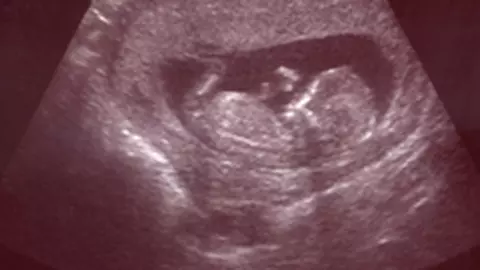

Placenta abruptio reprezinta separarea prematura a placentei de uter inainte de nastere.